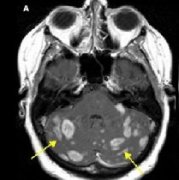

18F-FDOPAPET与胶质瘤复发转移及放射性脑损伤的鉴别诊断 鉴于MRI难以区分胶质瘤复发转移和放射性脑损伤,有两项研究分别报告了18F-FDOPA在上述两种鉴别诊断...